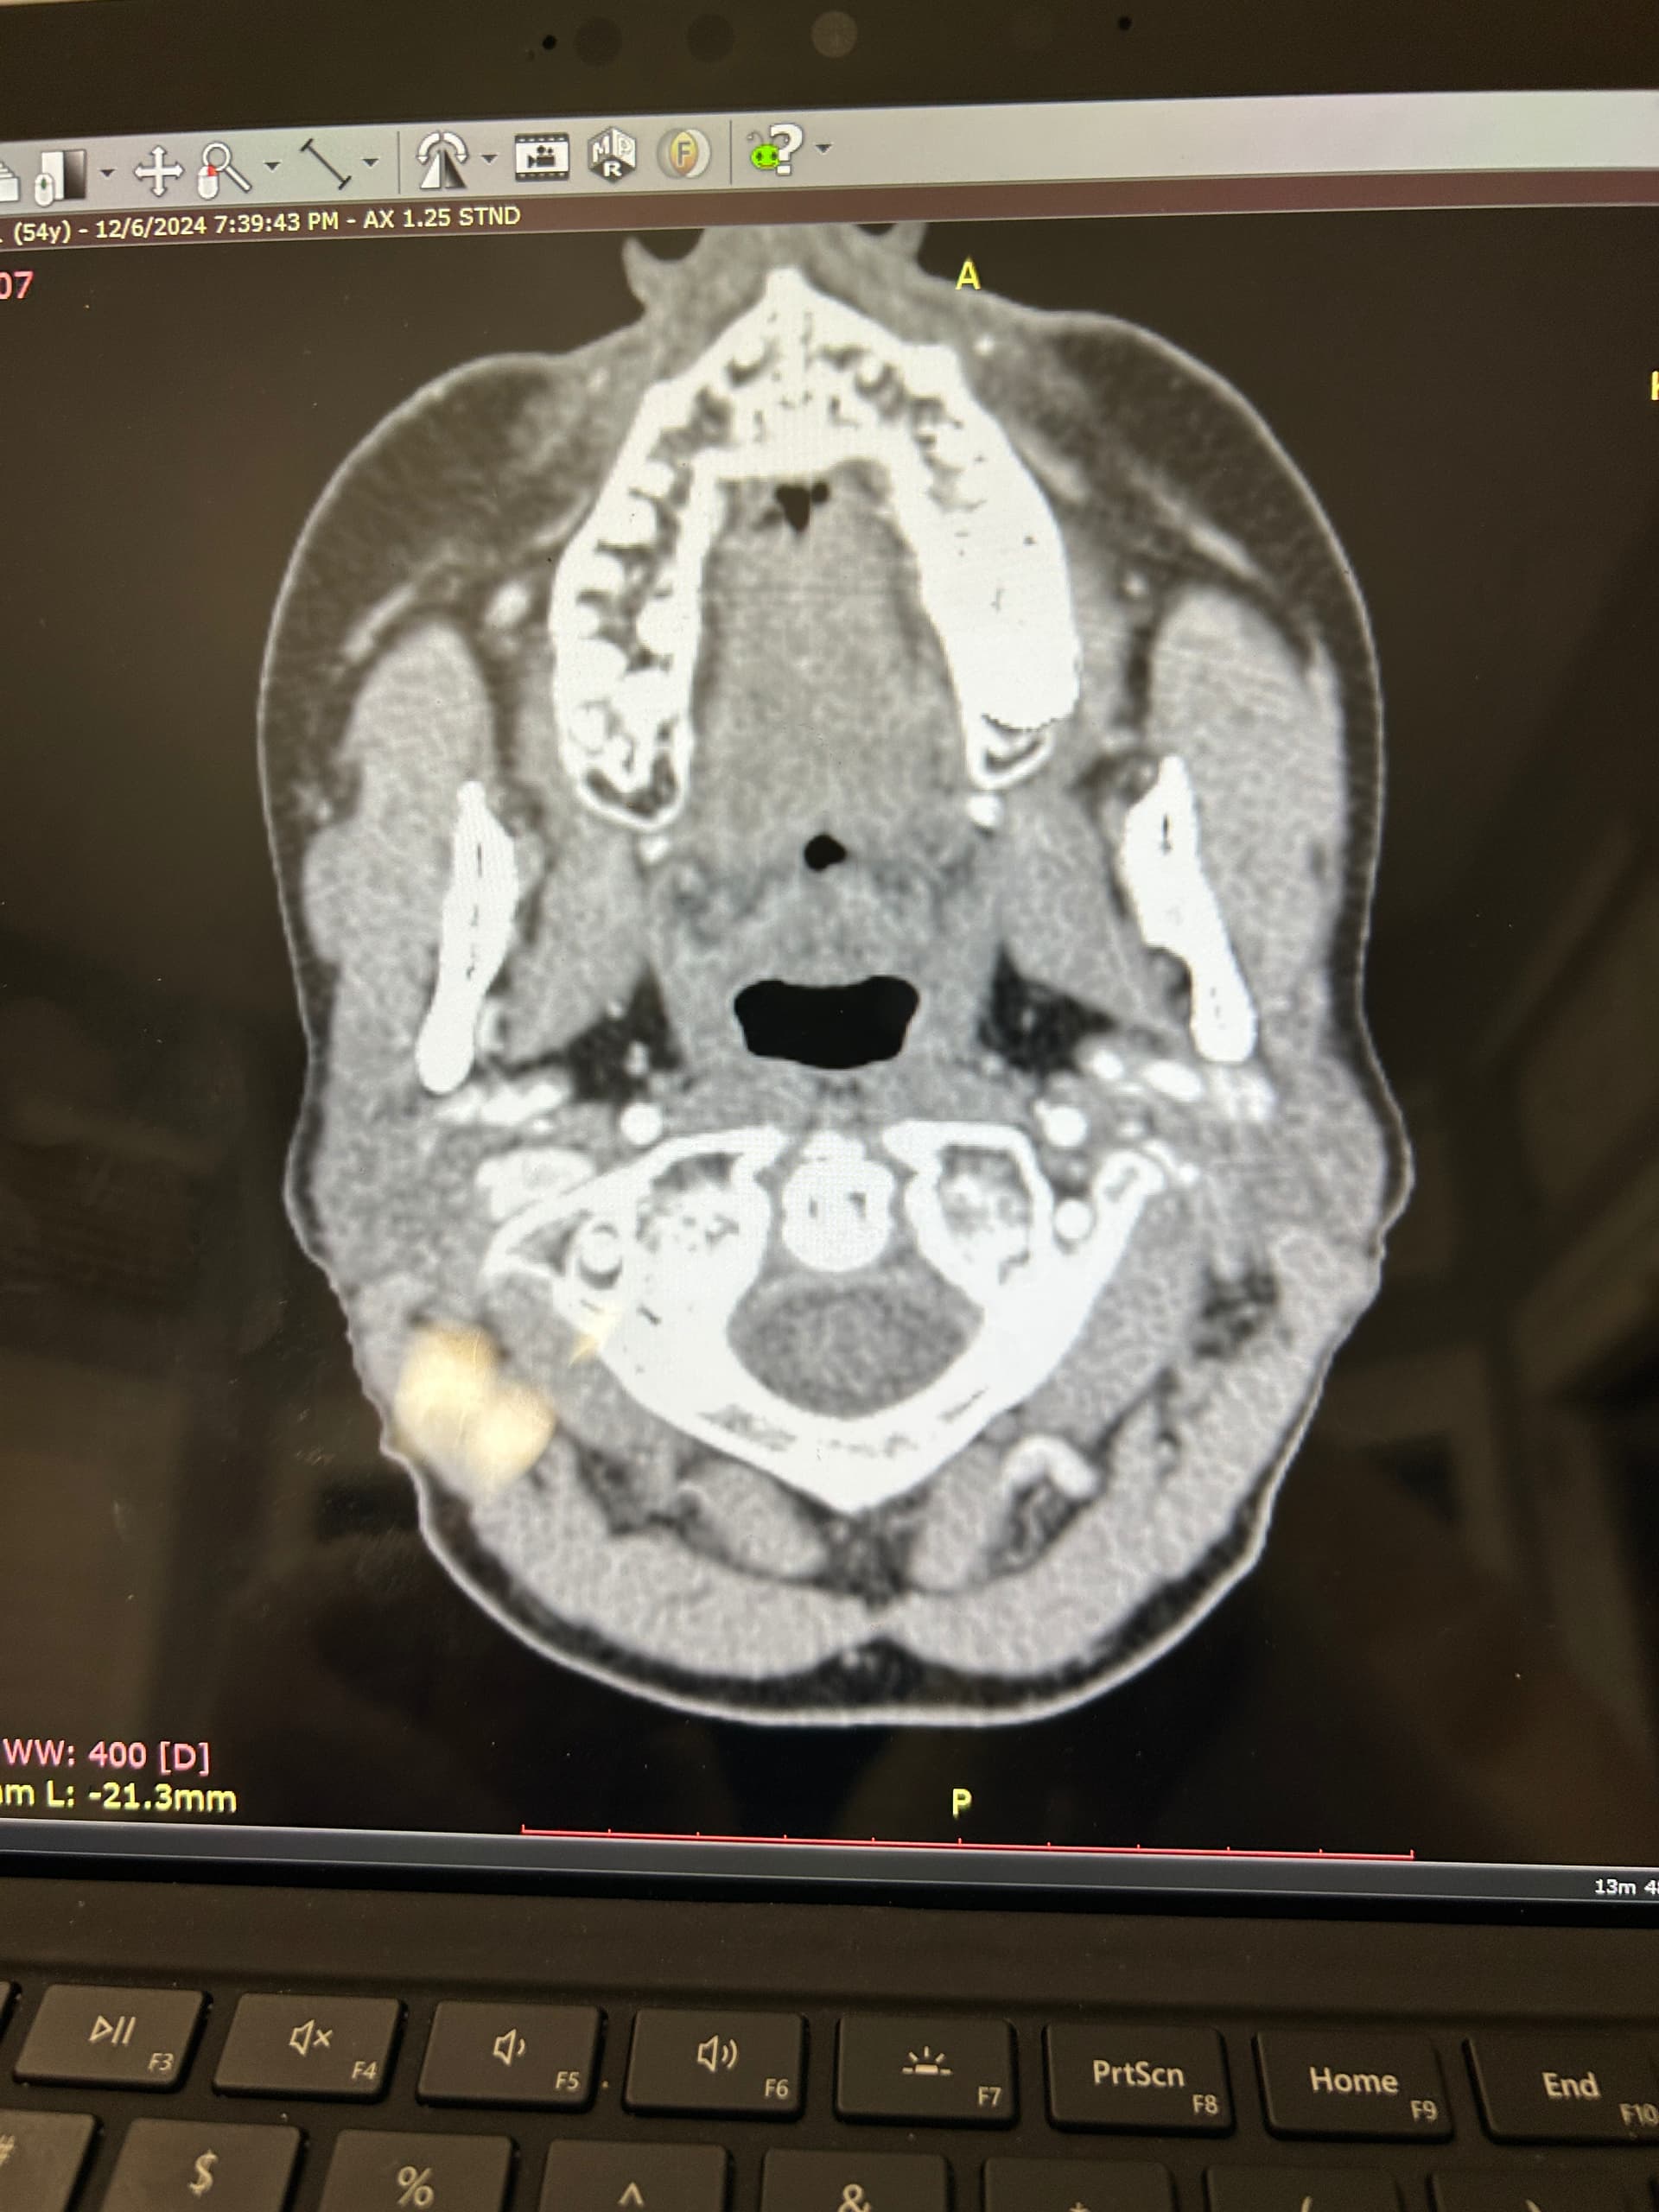

I’ve uploaded some photos. Some are repetitive but I know some in this group are skilled in reading these.

I also added some 3D photos. My left JV looks extremely narrow at around C3. Does anyone else see that?

@Luckee7 - I’ve marked some vascular structures that are above & beneath your C1 vertebra that I haven’t seen before in other imaging so am not sure what they are or if they could be involved in causing symptoms. Those above C1 appear to be “sitting” on it which appears to be causing some minor compression of those sections. They could be collateral veins, & if so, then they’re likely contributing to skull base/occipital pain.